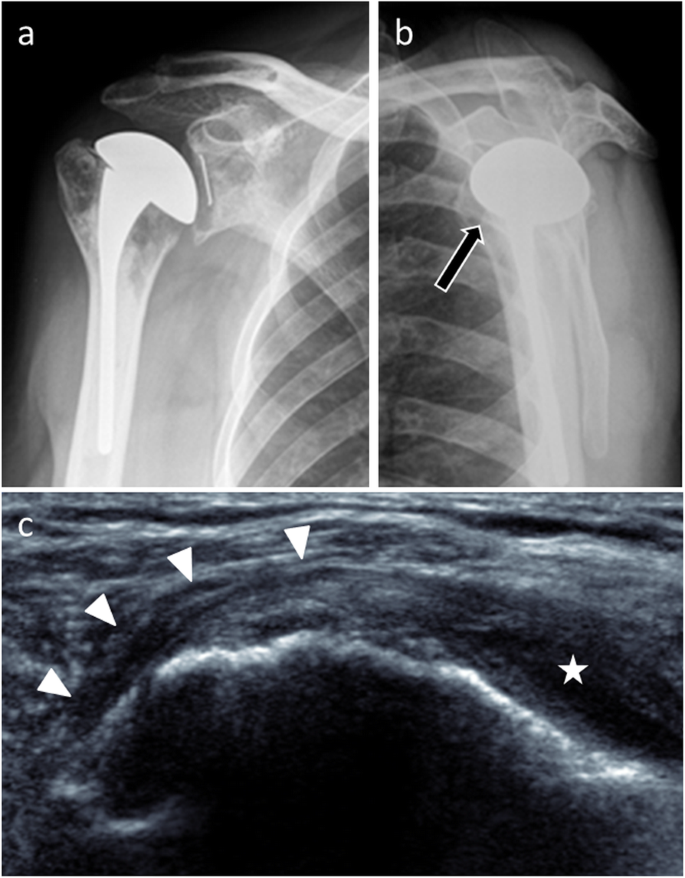

In imaging, ultrasonography helps diagnosis when it directly visualizes the tear [11] (Fig. 19). MRI also contributes to this as long as susceptibility artifacts do not interfere with interpretation. In CT, rupture usually cannot be seen directly because of the hardware artifacts, but a fatty degeneration of the rotator cuff is considered as a reliable indirect sign of a rotator cuff tear (Fig. 20). On standard radiographs, supraspinatus tear is suspected when the distance between the top of the humeral prosthesis and the acromion is less than 5 mm [9]. Anterior translation of the humeral head on anteroposterior and scapular Y views will suggest a subscapularis insufficiency.

Anteroposterior (a) and scapular Y (b) radiographs in a 52-year-old woman with total shoulder arthroplasty and anterior instability show an anterior translation of the humeral head. c Axial CT image confirms this anterior translation (thick arrow). d Axial CT image with smooth reconstruction filter shows fatty degeneration of the subscapularis muscle (thin arrow). All these elements lead to suspicion of subscapularis tendon tear and this tear was confirmed during surgery